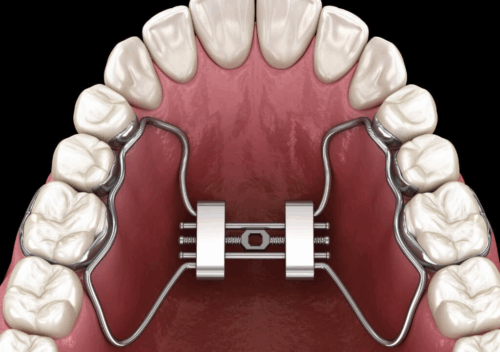

A Ortodontia e a Ortopedia Funcional dos Maxilares tratam as irregularidades dentais e faciais por meio do uso de aparelhos fixos e removíveis. Nosso objetivo é conseguir mudanças significativas no sorriso e, consequentemente, na vida das pessoas.

Existem várias técnicas utilizadas atualmente, por isso cada paciente recebe um diagnóstico específico e através deste elaboramos o seu plano de tratamento.